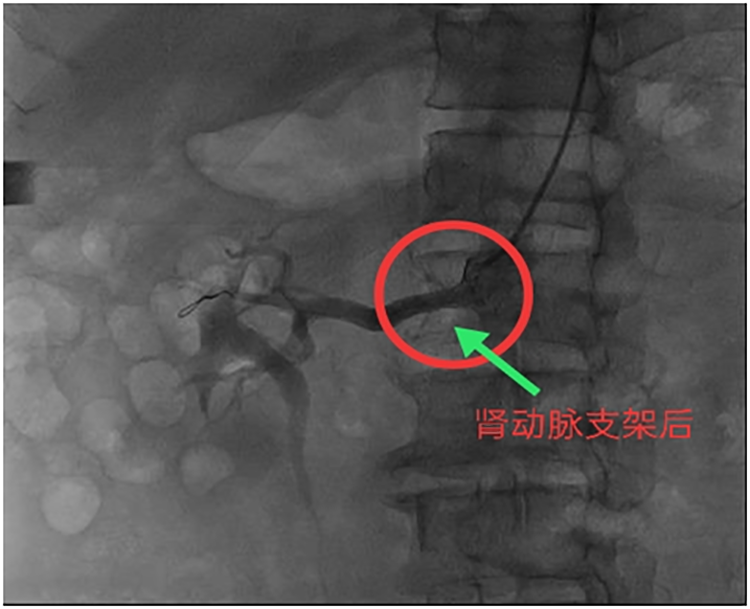

近日,我院介入诊疗科成功为一位肾动脉狭窄并发顽固性高血压患者行肾动脉支架植入治疗,效果显著。患者男性,71岁,糖尿病病史3年,高血压病史8年,每天坚持服用贝那普利20mg,非洛地平10mg降压治疗。但经常因血压波动,降压药物用量难于掌握而困扰患者。2020年7月21日患者因双下肢疼痛入院治疗。入院后查双下肢动脉造影,显示动脉病变较轻,无需特殊处理,强化药物治疗即可,但发现右肾动脉狭窄非常严重,至此查出导致顽固性高血压的真正原因,遂于2020年7月24日在局麻下行肾动脉球囊扩张及支架植入术。术后患者无不适,生命体征平稳,于7月29日出院。术后一月随访,患者已逐渐停用降压药物,血压波动在正常范围,效果非常满意。

肾动脉狭窄发病隐匿,不易早期发现,大部分患者都是在发生难治性高血压或缺血性肾病等疾病时,经检查才发现此病。肾动脉狭窄是继发性高血压最常见的原因之一。经肾动脉造影能准确显示狭窄部位、程度、病变范围,是诊断肾动脉狭窄的“金标准”。目前,肾动脉介入治疗已成为动脉粥样硬化性肾动脉狭窄的首选治疗方法,可有效治疗肾动脉狭窄并发的难治性高血压,显著改善患者临床症状,提高生活质量。